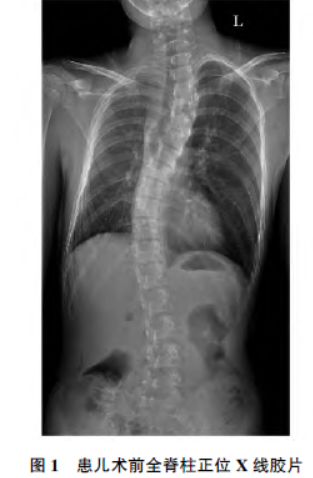

入院查体:脊柱上胸段左侧凸,形成剃刀背畸形,胸腰段右侧凸,左肩较右肩高;漏斗胸畸形,余心肺查体未见异常。全脊柱正侧位X 线片(图1)示脊柱侧凸,上胸段左凸畸形,Cobb 角40°,胸腰段右凸畸形,Cobb 角39°。超声心动图